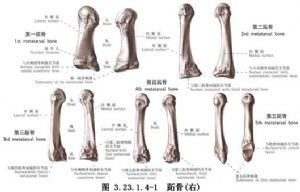

对无移位的跖骨骨折,只需用短腿石膏或石膏靴固定6周。对有移位的跖骨骨折,应尽早手法复位和石膏固定,如不能获得准确复位,则应行手术复位和内固定。手术相关解剖及影像表现见下图(图3.23.1.4-1~3.23.1.4-5)。